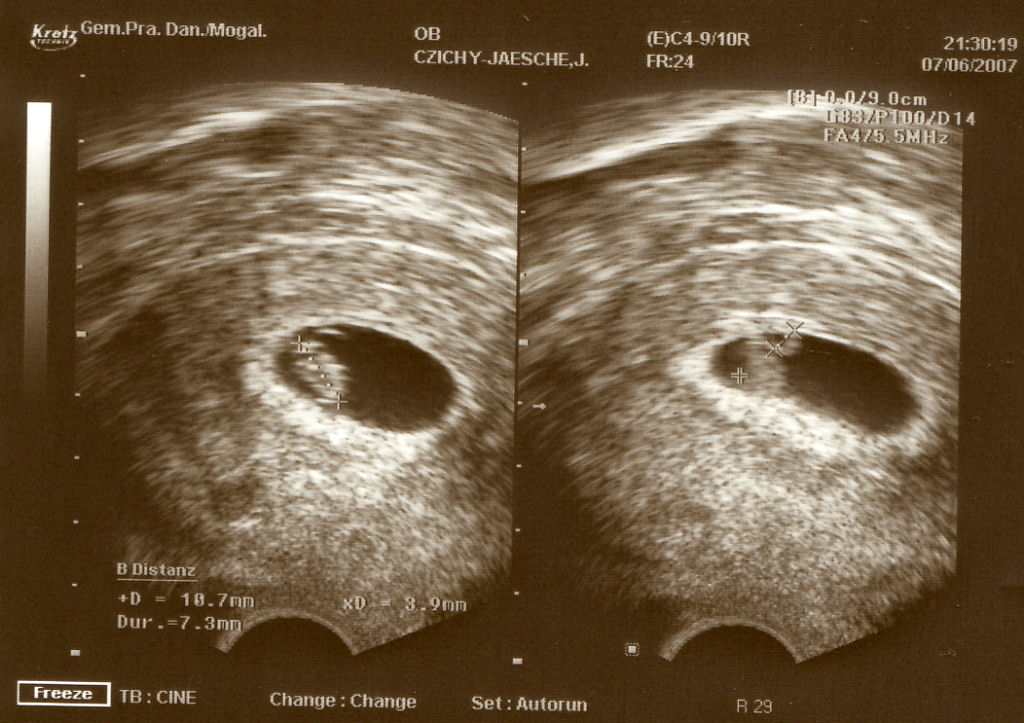

@jaeschie: süßes bild von deinem Zwerg! kann man ja schon langsam richtig was erkennen.